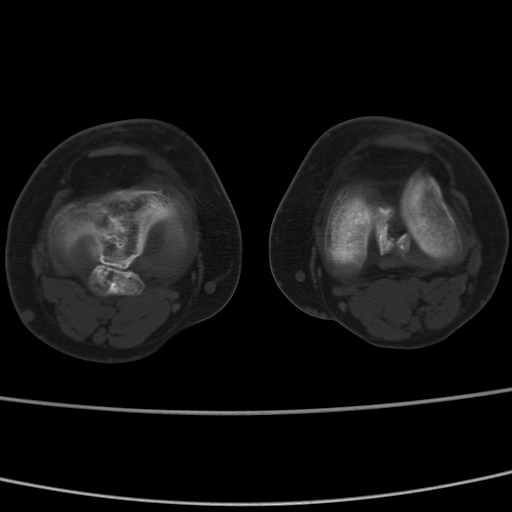

女性,50岁。【请提供患者临床症状体征】

右膝关节退行性改变,关节游离鼠。

右膝关节退行性改变,滑膜黏液囊钙/骨化并游离。